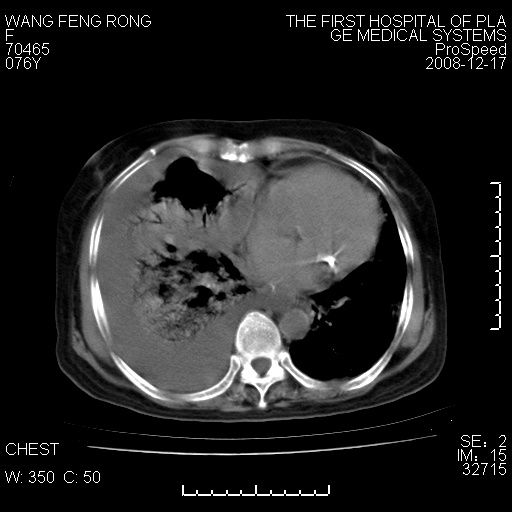

右肺大部实变,其内可见支气管影,但分支减少,宽窄不均,走行僵直,同侧胸腔大量积液;纵隔内见多发淋巴结影,但淋巴结大部有钙化;主动脉壁钙化;临床上病人咳嗽、消瘦。所以我考虑:1、结核(依据:右下肺实变,纵隔内淋巴结符合结核表现,同侧并发胸膜炎表现);2、支气管肺泡癌(依据:实变的肺组织内支气管分支减少,宽窄不均,走行僵直,没有把它放在第一诊断是因为没有看到明显肿大的淋巴结);3、动脉硬化(主动脉壁钙化就支持这个诊断)。

1)考虑两肺炎症感染;不排除肺泡癌可能。2)两肺间质纤维化。3)右侧胸腔积液。

病理结果,肺泡癌